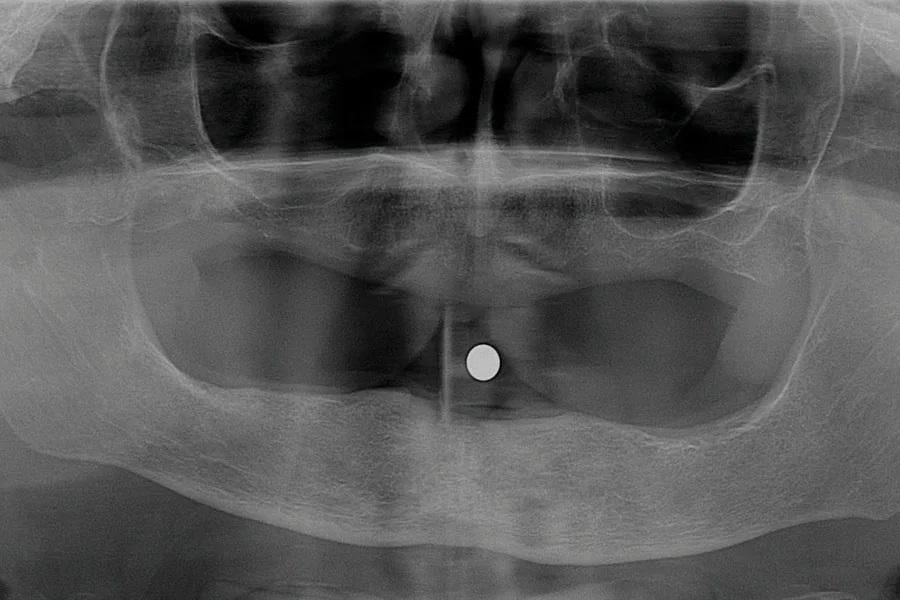

Фото 2: Рентгенограмма до лечения.

Пациентка испытывала сильный страх перед стоматологическим лечением, что усугубило состояние ее зубов. У нее были частичные съемные протезы на верхней и нижней челюстях, а оставшиеся зубы имели запущенный пародонтит, кариес и подвижность. На панорамном снимке все зубы были признаны не подлежащими восстановлению (Фото 2). Учитывая финансовые ограничения и страх перед хирургическим лечением с установкой имплантатов, было принято решение о цифровом изготовлении немедленных протезов. После заживления тканей временные протезы должны были быть заменены на окончательные. Из-за страха пациентка вернулась к лечению только через 3 года.